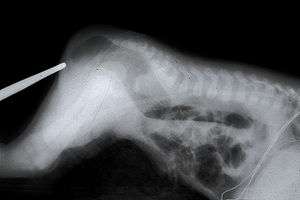

An X-ray showing imperforate anus | |